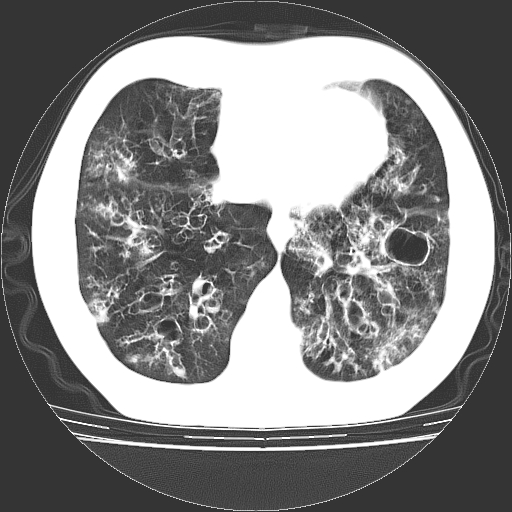

以下是引用zyx168在2006-12-4 15:30:00的发言:[br]经典!支气管肺囊肿并感染。

以下是引用dyqct在2006-12-4 17:11:00的发言:[br]典型的囊状支扩合并感染。

以下是引用liaoqiang在2006-12-4 16:12:00的发言:[br]局部肺叶内可见扩张的支气管壁,考虑为支扩。部份囊样影内有小液平和肺内散布斑片征影、小结节及纤维灶,提示支扩伴感染,且由于局部呈现有树芽征感染以结核可能性大。

以下是引用zhoucan076在2006-12-4 16:48:00的发言:[br]囊状支扩合并感染